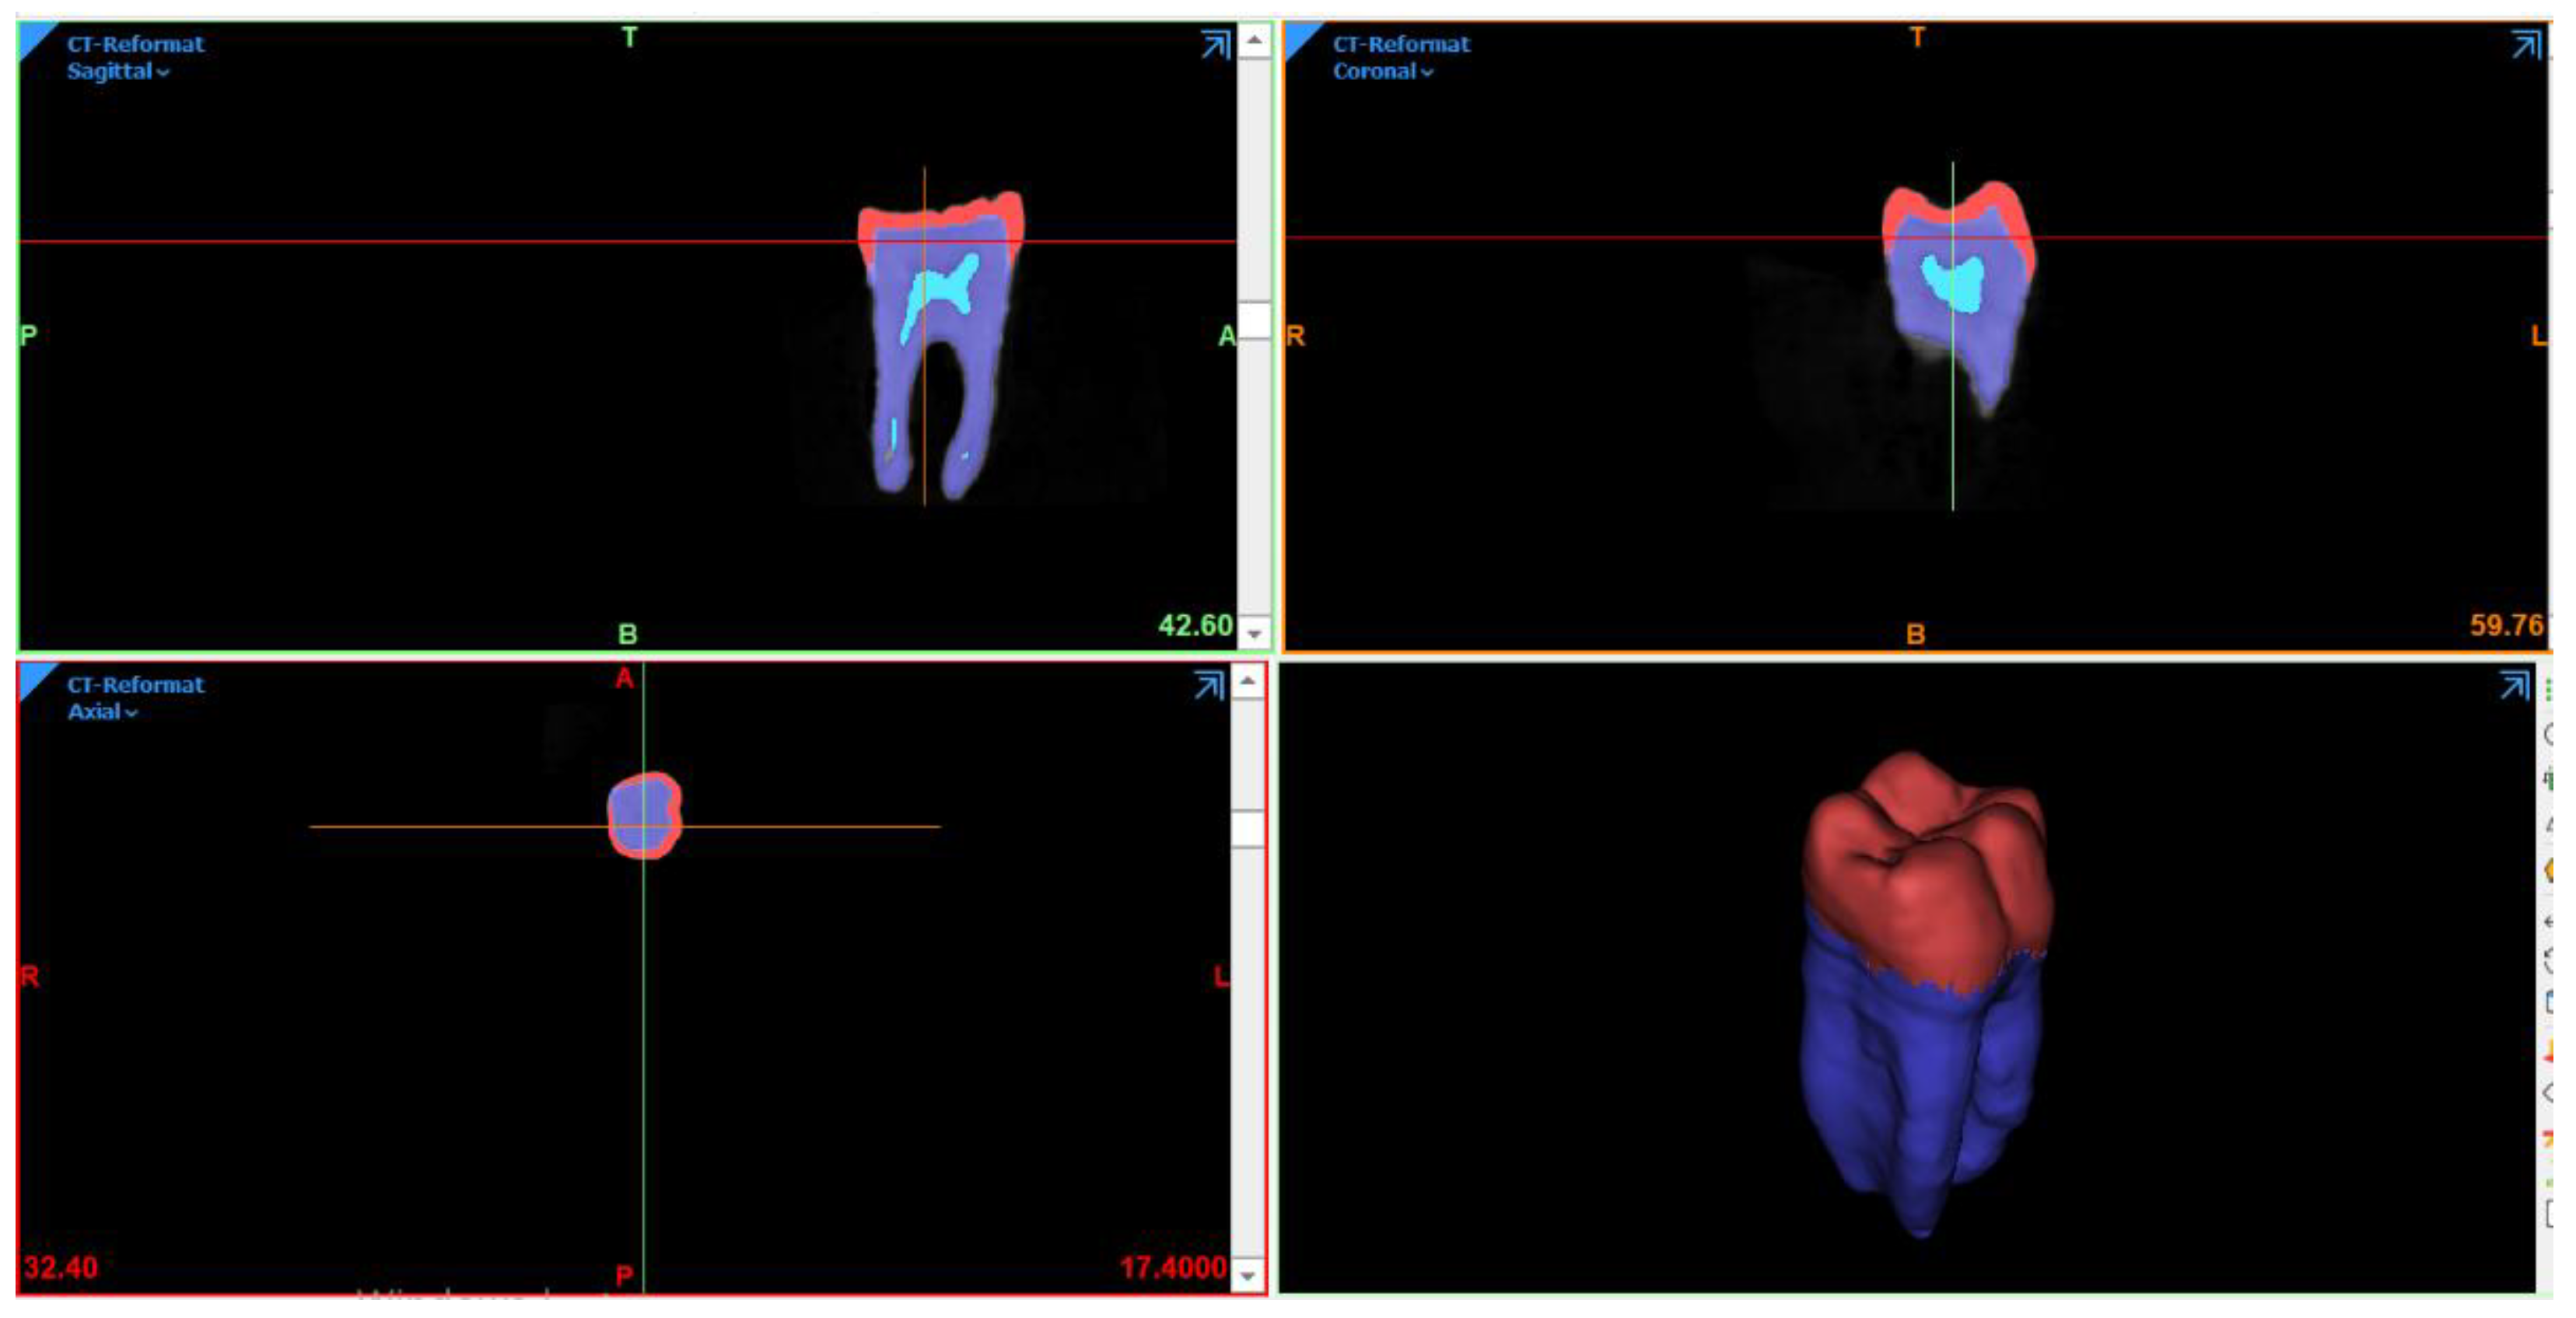

2.1. FEA Modeling